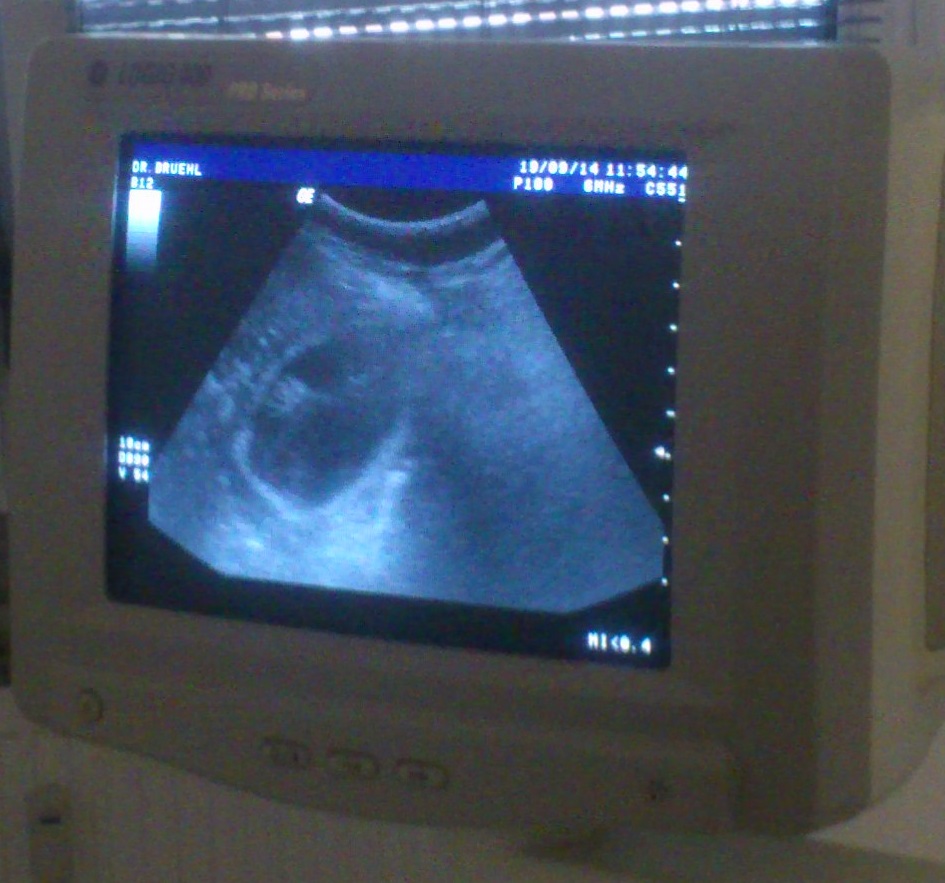

19.09.2014

Ultraschall

Also genau vor einer Woche da waren wir schon mal alle gemeinsam bei diesem netten Herrn, der mit so einem glibbrigen Teil an meinem Bauch rumgekitzelt und dabei auf einen Bildschirm geschaut hat.

Und wieder das selbe Spielchen.

Erst Glibber, dann "Tja".

Wir wollten ihm dieses Mal schon glauben, doch dann sagte er plötzlich was anderes.

Nicht mehr "Tja", sondern "O-Oh".

Und dann: "Da haben wir doch was".

Und dann deutete er auf den Bildschirm von dem Glibberkramteil:

Und da konnte man es genau sehen ... und das hat sich sogar schon bewegt !!

Soviel zum Thema 95 Prozent.

Er meinte noch, es könne ein Einzelkind werden. Aber das glaube ich auch noch nicht.